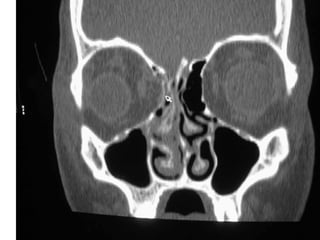

Radiographic Evaluation

• CT scan of the orbits

• Plain films not useful due to a high rate of

false negatives and non-diagnostic studies